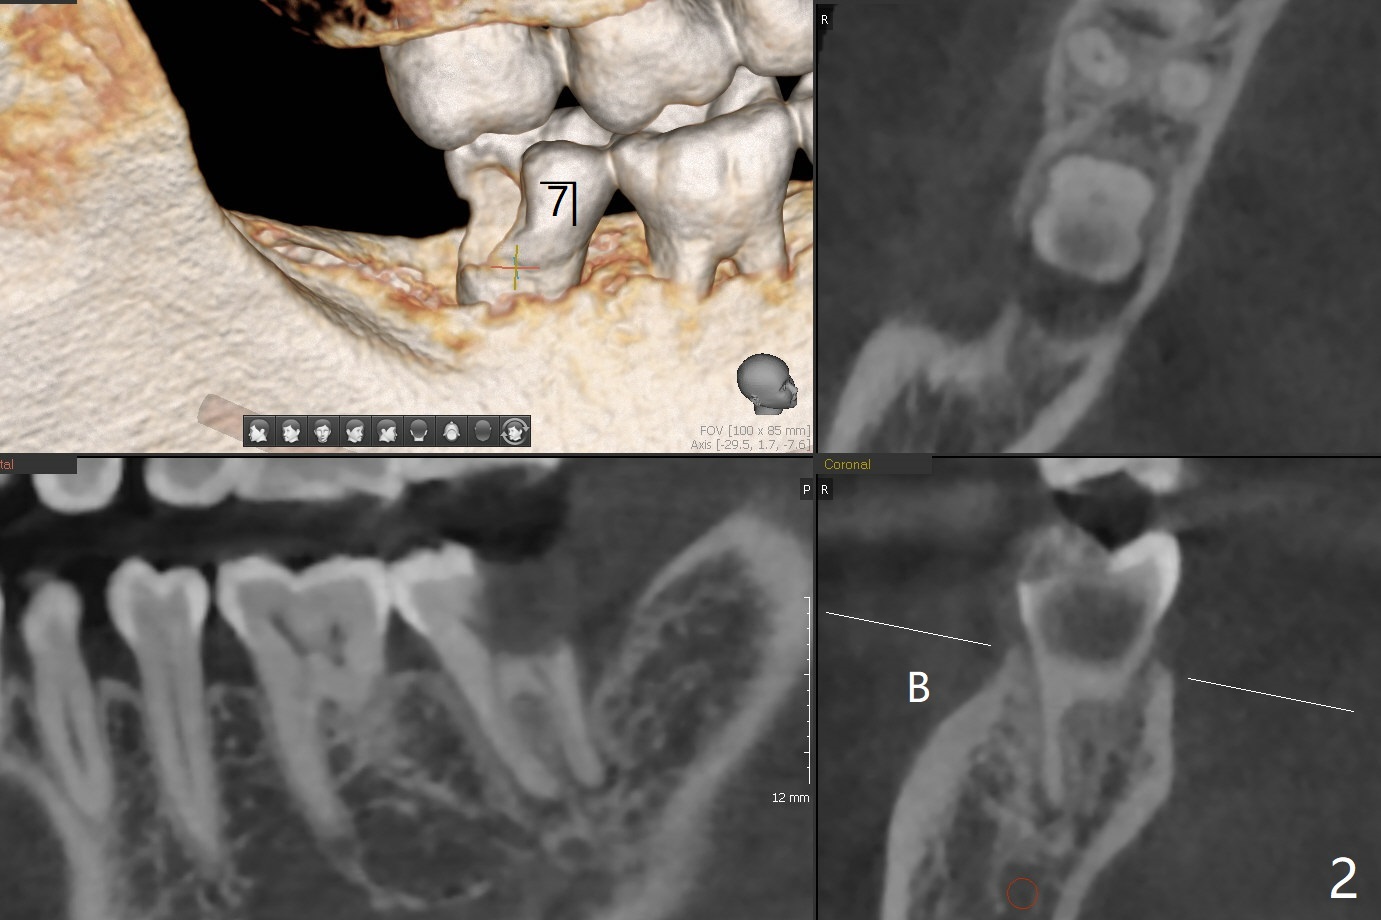

56岁女右侧不好咀嚼,右下7远中龈下龋齿(图一,二),能保留吗?Implant or rct plus crown lengthening, either way is fine, but implant may be more straightforward (Robert). Hi, Jennifer: I love the way you design implant in the mesial slope of the lower 2nd molar (Fig.1,4). When I place an implant free hand, I make sure that the long axis of the implant is 5 mm from the distal surface of the 1st molar (half of the mesiodistal width of the 2nd molar, Fig.5) as long as the implant is not too close to the neighboring root (black dashed line of Fig.5). PAs are taken several times intraoperatively to monitor the distal drifting (Fig.6 open arrow) of the osteotomy (red line). In my opinion, the drifting exists with guided surgery, especially the change of angulation. Can you intentionally move the implant mesially (Fig.7 open arrow) by 0.5-1 mm depending upon bone density or tilt the implant mesial coronally? Thanks for your consideration.